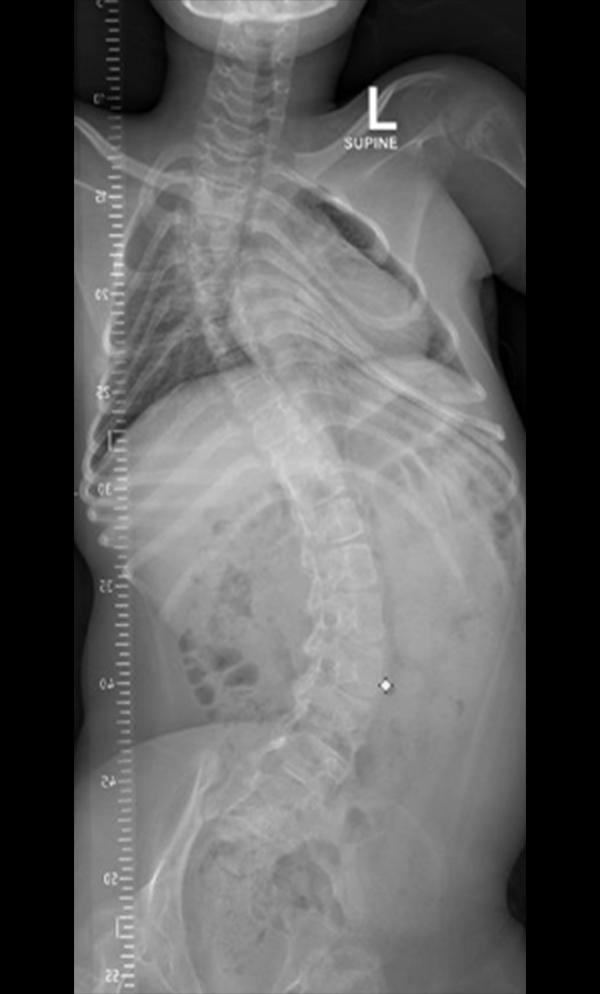

Internationally, he has held Senior Consultant and Leadership appointments across the UAE and Germany, with deep, hands on expertise across the full spectrum of Spine Care including Complex Deformity Correction (Scoliosis/Kyphosis and Sagittal Balance), Paediatric Spine Deformities (including Growing-Rod Techniques & VBT (Vertebral Body Tethering)), Degenerative Conditions (Cervical/Lumbar Disc Disease, Stenosis, Radiculopathy) and Spine Trauma and Tumours.

• Scoliosis surgery with small incisions using flexible correction technology (VBT) and growth-preserving techniques such as remotely controlled magnetic growing rods

• Scoliosis for children and adults

Gallery : Before - After